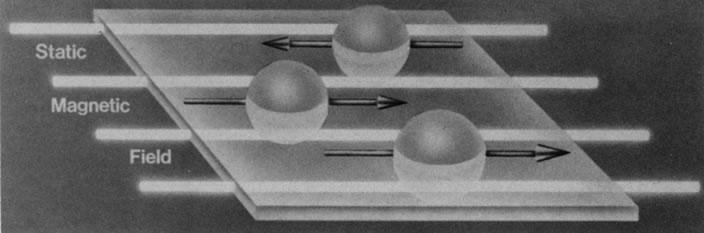

Hydrogen, which contains a single proton, has the largest magnetic moment of all stable atomic nuclei and is highly prevalent throughout biologic tissues. For these reasons, hydrogen forms the basis for MRI and exemplifies its principles. In nature, the magnetic moments of the hydrogen nuclei in biologic tissues are randomly oriented and therefore exhibit no net magnetic effect (Fig. 2). When these nuclei are placed in a strong static magnetic field, such as that produced in an MRI unit, they line up parallel or antiparallel to the field. Slightly more align parallel to the main magnetic field, because this is a lower energy state, and produce a net magnetic vector in this direction (Fig. 3).1,5,8